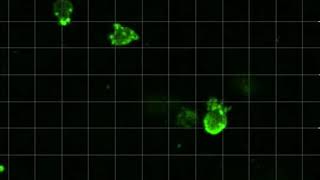

Invasive breast cancer cells push through ‘tissue’ video

Invasive breast cancer cells push through ‘tissue’

Invasive breast cancer cells push through ‘tissue’